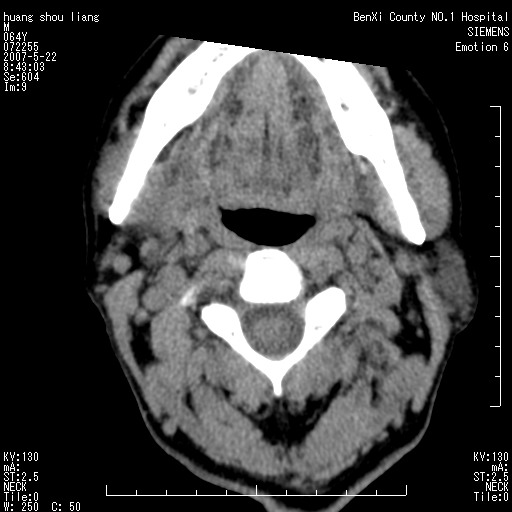

男性,64岁。颈部包块8年。最近增大。

对不起大家,可能是片子发太多有点乱,正常腮腺在下颌角的外侧,颌下腺在下颌体的中部内侧,本例在下颌角内侧偏下,和腺体一点关系都没有,从vrt和mpr上可以很明显看出来,再者肿块是好多粘连在一块的,大家在仔细看看,左侧可能也是吧,我还是考虑为肿大的淋巴结融合在一块,但性质??????

右侧腮腺下部均匀软组织密度肿块,外形不规则,与周围组织分界清晰,考虑右侧腮腺混合瘤或多形性腺瘤。

大家好,病理结果出来了,如大家所说,颌下腺混合瘤。

唉,解剖没学好吧,我诊断错了,不过还是有些不理解回去我在多看看书,谢谢大家的参与,以后我还会奉献好的病例。